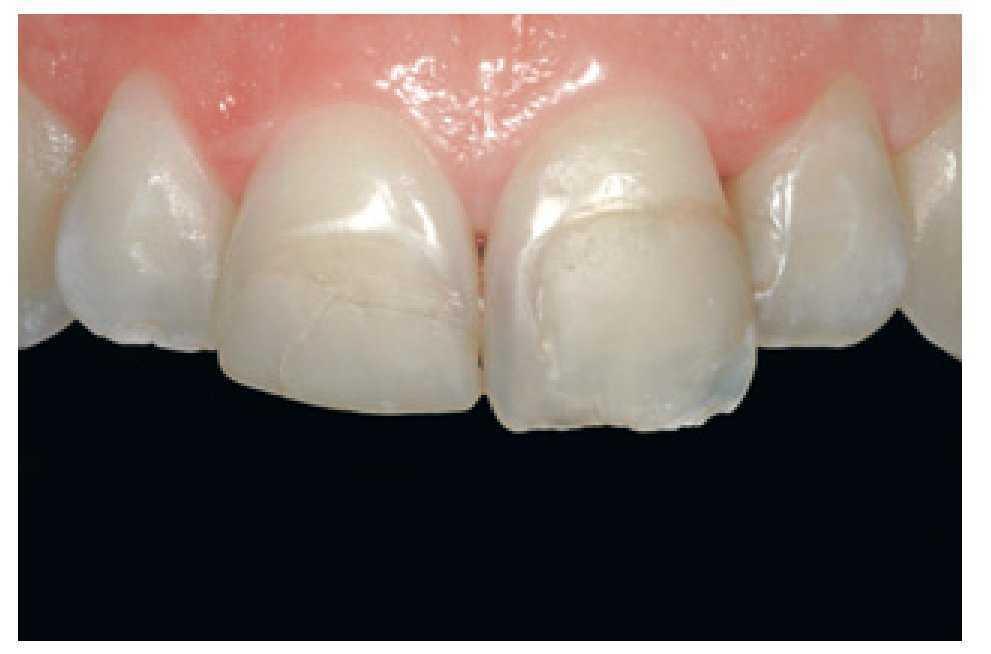

La paciente era una mujer de 32 años de edad con elevadas exigencias estéticas que acudió a la clínica necesitando un tratamiento de urgencia, tras haber pegado ella misma un fragmento de composite con cianoacrilato a una restauración preexistente en el diente número 11. No mencionó dolor ni hipersensibilidad térmica, pero sí se quejó de un leve sangrado gingival esporádico. La exploración clínica (figura 32) reveló la presencia de una serie de restauraciones de resina en los dientes 11, 21 y 22, incongruentes en términos de perfil de emergencia, color y grado de acabado, con márgenes teñidos infiltrados por caries secundaria. Más importante que esto, las restauraciones eran estética y anatómicamente deficientes. La exploración de los tejidos gingivales reveló la presencia de una gingivitis marginal causada por la deficiente higiene de la paciente y un gran acúmulo de placa bacteriana. Aún así, el aparato periodontal aparentemente estaba en buen estado.

Figura 32 Imagen previa al tratamiento que muestra el intento de la paciente de pegar un fragmento fracturado de composite en el diente número 11, alteraciones de las restauraciones existentes y evidencia del grado de contaminación por placa bacteriana.